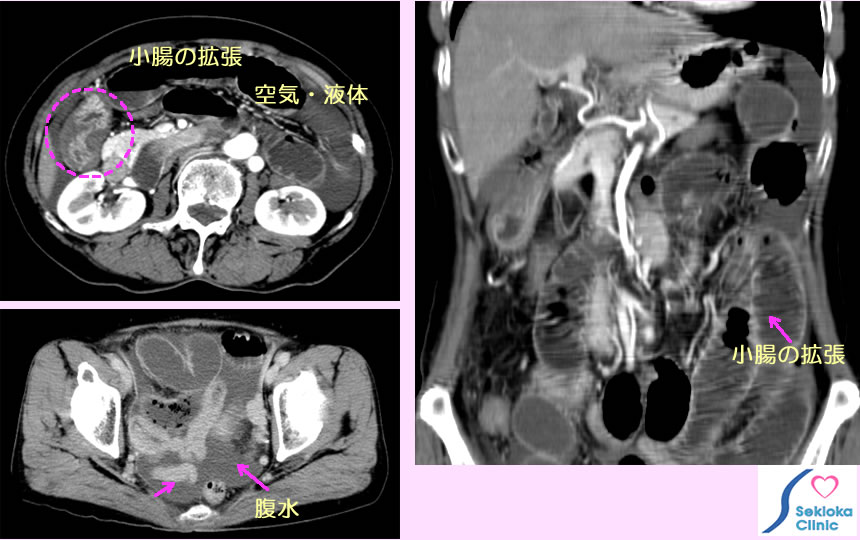

症状、腹部の触診で腸閉塞を疑い、X線撮影、CT、より詳細はMDCTで診断されます。 添付画像は小腸の著明な拡張、液体、空気の貯留を認めますが大腸の拡張は見られません。上段左の画像の破線円内に腸の狭窄、閉塞と思われる所見を認めます。

治療

掲載例は開腹手術にて腸閉塞を解除。軽症の場合は管を鼻から胃、腸に挿入して空気、液を吸引排出して減圧することで手術をせずに回避できることもあります。本例は以前の虫垂炎の手術が原因で腸閉塞が発症したものでした。